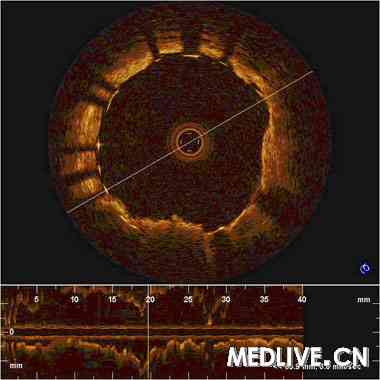

OCT检查示:右冠不稳定脂质斑块伴严重狭窄。(图2:不稳定脂质斑块;图3:严重狭窄)

图3 OCT检查示严重狭窄